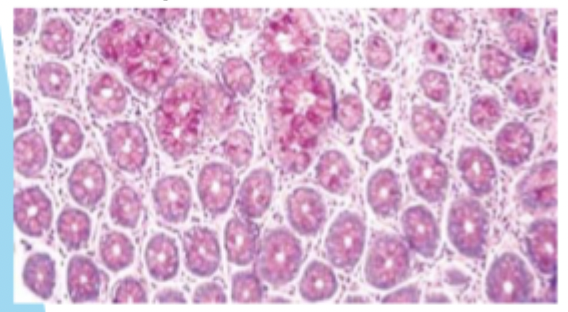

Microtomy

Ability to cut extremely thin slices (sections) of tissue

Purpose of microtomy

Enables transparency of stained tissues and cells when viewing microscopically

Routine histolofgy sections are cut at…

3–4μm thickness